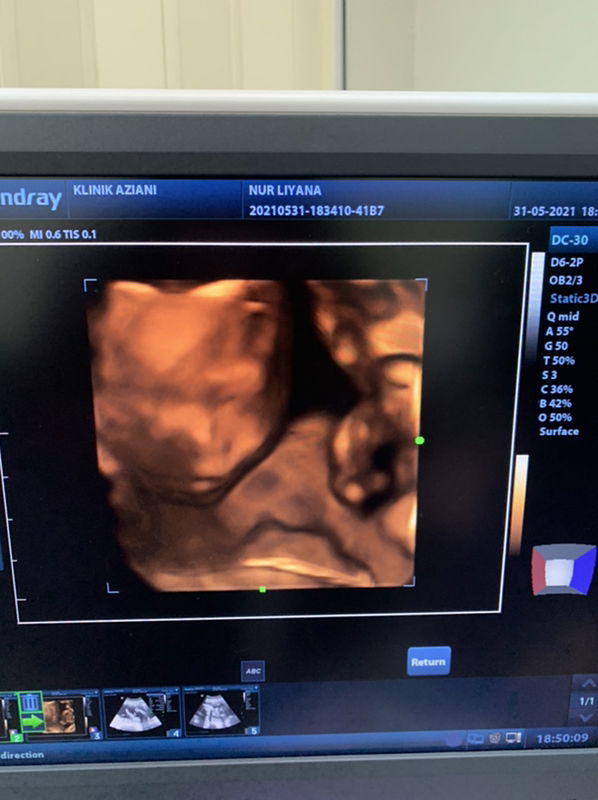

Waktu ibu berbadan dua, mesti ada bau yang ibu tidak suka kan?🤢 Kadang sebelum berbadan dua, dia suka je bau tu🥰 Tiba-tiba bila mengandung, tak boleh pula🥺😫 Ni bukan buat-buat ya, tapi memang betul🤧 Jom kongsikan bau apa yang paling busuk bagi ibu mengandung?🤰